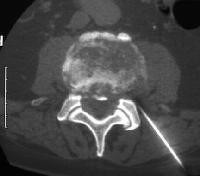

With CT -guided (computerized tomography) pain therapy I am able to offer you a highly effective and gentle treatment method, which is the most appropriate kind of pain therapy for the spinal column (slipped spinal discs, spinal disc protrusions, wear-and-tear of minor vertebral joints) and shoulder arthritis.

With computerized tomography it is possible to obtain an exact localisation of the origin of the pain in the spinal column or the joint. For the treatment you either lie simply on your stomach or back in the computerized tomography scanner. Once the exact point of entry has been determined, the skin is disinfected, after which a mixture of drugs consisting of a local anaesthetic and a cortisone preparation is injected with a fine hypodermic needle. The advantage of the use of computerized tomography is that it enables the exact placement of the injection with millimetre precision. As the drugs that inhibit inflammation take effect exactly at the point at which the damaged nerves or spinal joints are located, the body is clearly burdened to a lesser extent compared to other treatment methods (taking pills or infusions). A small amount of contrasting agent that contains iodine is required to visualise the correct distribution of drugs to guarantee an exact positioning.